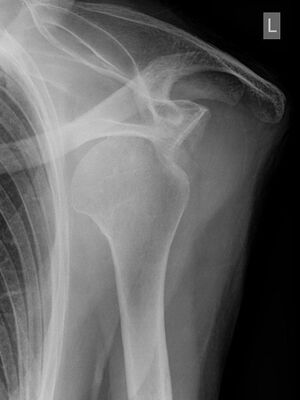

Schulterverrenkung

Röntgenbild einer ausgerenkten Schulter - Hellerhoff commons.wikimedia.org, CC BY-SA 3.0

Eine Schulterverrenkung wird häufig durch einen Sturz auf den ausgestreckten Arm oder durch einen starken Zug am Arm ausgelöst. Diese Verletzung treten häufig beim Skifahren, Eishockey, Handball oder Turnen auf.

Bei einer „ausgekugelten“ Schulter steht der Oberarm seitlich vom Körper ab, die normalen Umrisse des Schultergelenks sind verändert, der ausgerenkte Oberarmkopf und die Gelenkpfanne sind tastbar.